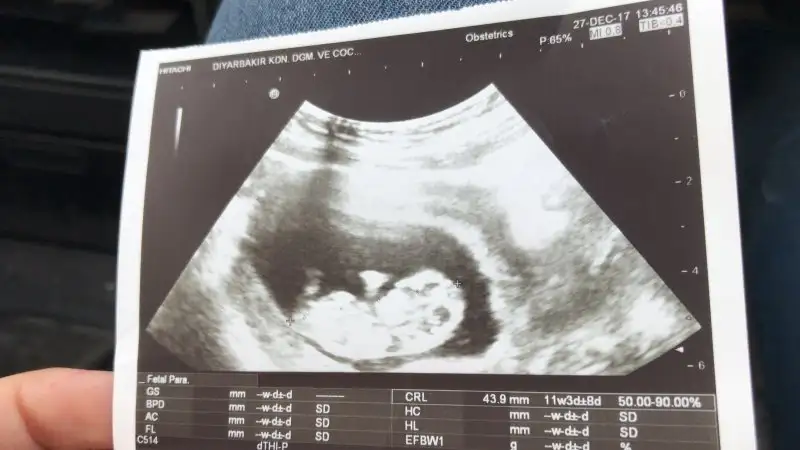

Mrb ben 13 haftalıkken kontrolde bebek çok hareketliydi doktor bacak arasına göre kıza benzetti 3 hafta sonra gel kesinleştirelim dedi sizce yanılma olur mu.ayrıca sonradan farkettim bebeğimin resminde üç beyaz nokta var sizce o ne olabilir